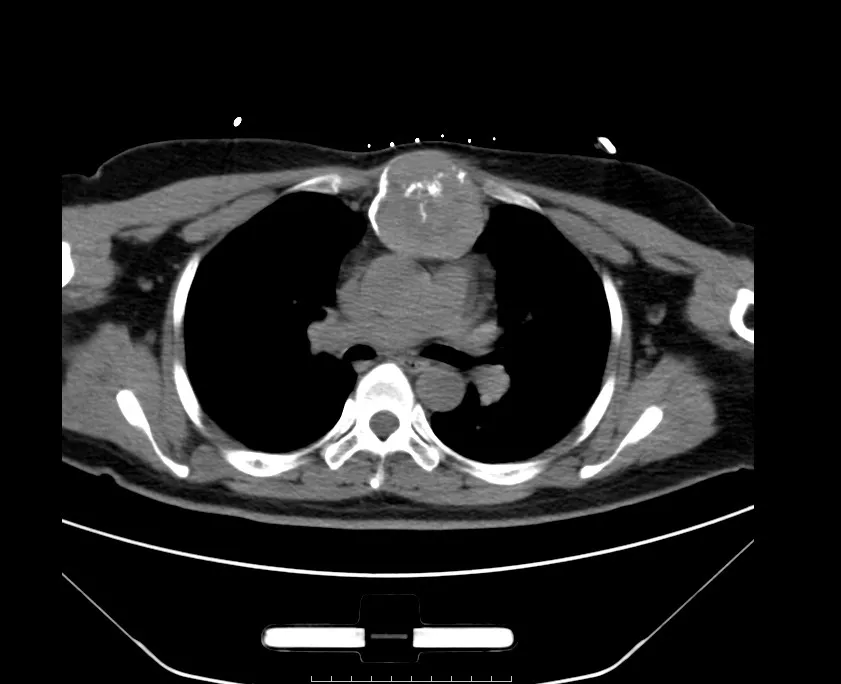

完善相关化验检查后,患者CT结果回报:胸骨柄占位性病变,考虑软骨源性肿瘤,软骨肉瘤可能。在术前的关键筹备阶段,我科为患者精心安排了肿物活检,旨在通过高度精准的微创技术,直接触及病变核心区域,快速准确地明确肿物性质、类型及分化程度,同时,穿刺时特别邀请血液内科主任包翠华医师团队会诊,由血液科医生直接从病变胸骨组织中精准提取骨髓标本,为肿瘤性质的判断提供了宝贵的病理学依据。

在排除了全身性相关疾病后,毛宇主任团队认为,手术切除是治疗胸骨肿瘤的第一选择,也是最佳选择,手术势在必行。但手术切除也面临着很大的风险和挑战。第一:患者胸骨肿物较大,胸骨柄紧邻两侧锁骨、肋软骨且肿物没有活动度,能否完整切除是难点;第二:肿物后方临近心脏,压迫心脏、主动脉弓及其分支及双侧胸腔,一旦侵犯或损伤则有大出血的致命风险;第三:胸骨柄、部分肋骨和肿物一并切除后,双侧锁骨和胸骨体之间会形成巨大缺损,这会造成前胸壁软化塌陷、胸廓活动功能受损及上肢、肩部活动障碍,患者生活质量会大受影响。为此,团队决定采用前沿的三维重建和3D打印技术,为手术制定更精准、安全的方案。三维重建是将患者的CT、MRI原始数据转化为三维可视化模型。这个模型如同一个“透视眼”,让医生能够清晰地看到病灶区域的每一个细节,包括肿瘤的大小、形状、位置以及与周围血管、神经、骨质等组织的关系,能够更加精准地规划手术路径,预测手术风险,制定出个性化的手术方案。同时利用3D打印技术,为患者量身定制适型多孔钛板,以满足其重建胸廓的需求。

术前CT